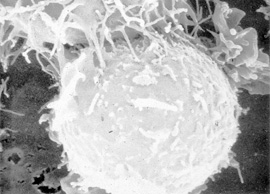

Von oben links greift eine so genannte Killerzelle eine Krebszelle an. Bild: DKFZ/Peter H. Krammer